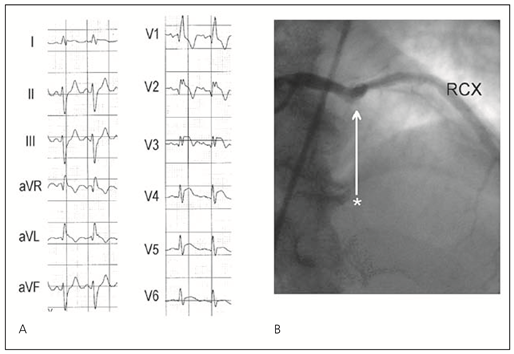

Das Vorhandensein von abnormalen Q-Zacken in Ableitungen mit ST-Hebungen im Eintritts EKG ist assoziiert mit einem grösseren Infarktareal und einer erhöhten Spitalmortalität [2]. Einige Patienten mit STEMI haben negative T-Wellen im EKG. Die T-Wellen-Inversion mit Verschwinden der ST-Hebung ist ein Zeichen der Reperfusion [12]. Patienten, die 2–6 Stunden nach Beginn der Symptomatik behandelt werden und T-Wellen-Inversionen in Ableitungen mit ST-Hebungen aufweisen, haben eine höhere Spitalmortalität als Patienten mit positiven T-Wellen. Dagegen haben Patienten mit negativen T-Wellen, die innerhalb 2 Stunden nach Beginn der Symptomatik behandelt werden keine erhöhte Spitalmortalität, dies im Gegensatz zu einer 5prozentigen Mortalitätsrate bei Patienten mit positiven T-Wellen [13]. ST-Hebungen mit negativen T-Wellen sind bei Patienten mit Beginn der Symptomatik vor mehr als 2 Stunden als Zeichen eines fortgeschritteneren Infarkt-Stadiums zu werten (Abb. 1 und 2).

Abbildung 2. 74jährige Patientin mit Schmerzbeginn vor 10 Stunden bei anteroseptalem Myokardinfarkt. A. Im Eintritts-EKG zeigt sich eine fehlende R-Progression mit ST-Hebungen von V1–V4 und negative T-Wellen bis V6. Diese Veränderungen sind als Zeichen eines fortgeschritteneren Infarkt-Stadiums zu werten. B. Koronarangiographisch zeigte sich ein funktioneller Verschluss des Ramus interventricularis anterior (RIVA) nach Abgang des ersten Diagonalastes (Stern). HS = Hauptstamm; RCX = Ramus circumflexus.